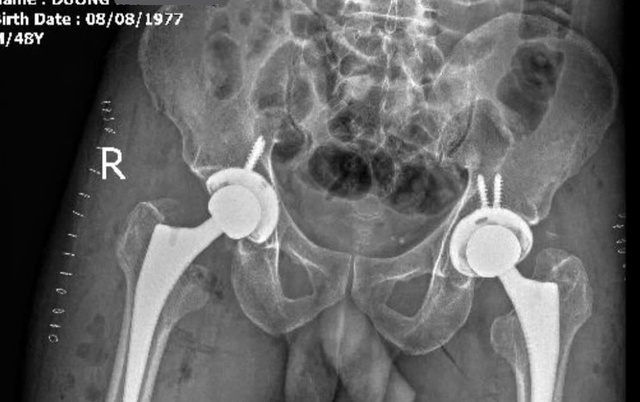

Hình ảnh chụp X-quang sau khi đã thay chỏm xương đùi 2 bên cho bệnh nhân

ẢNH: ĐT